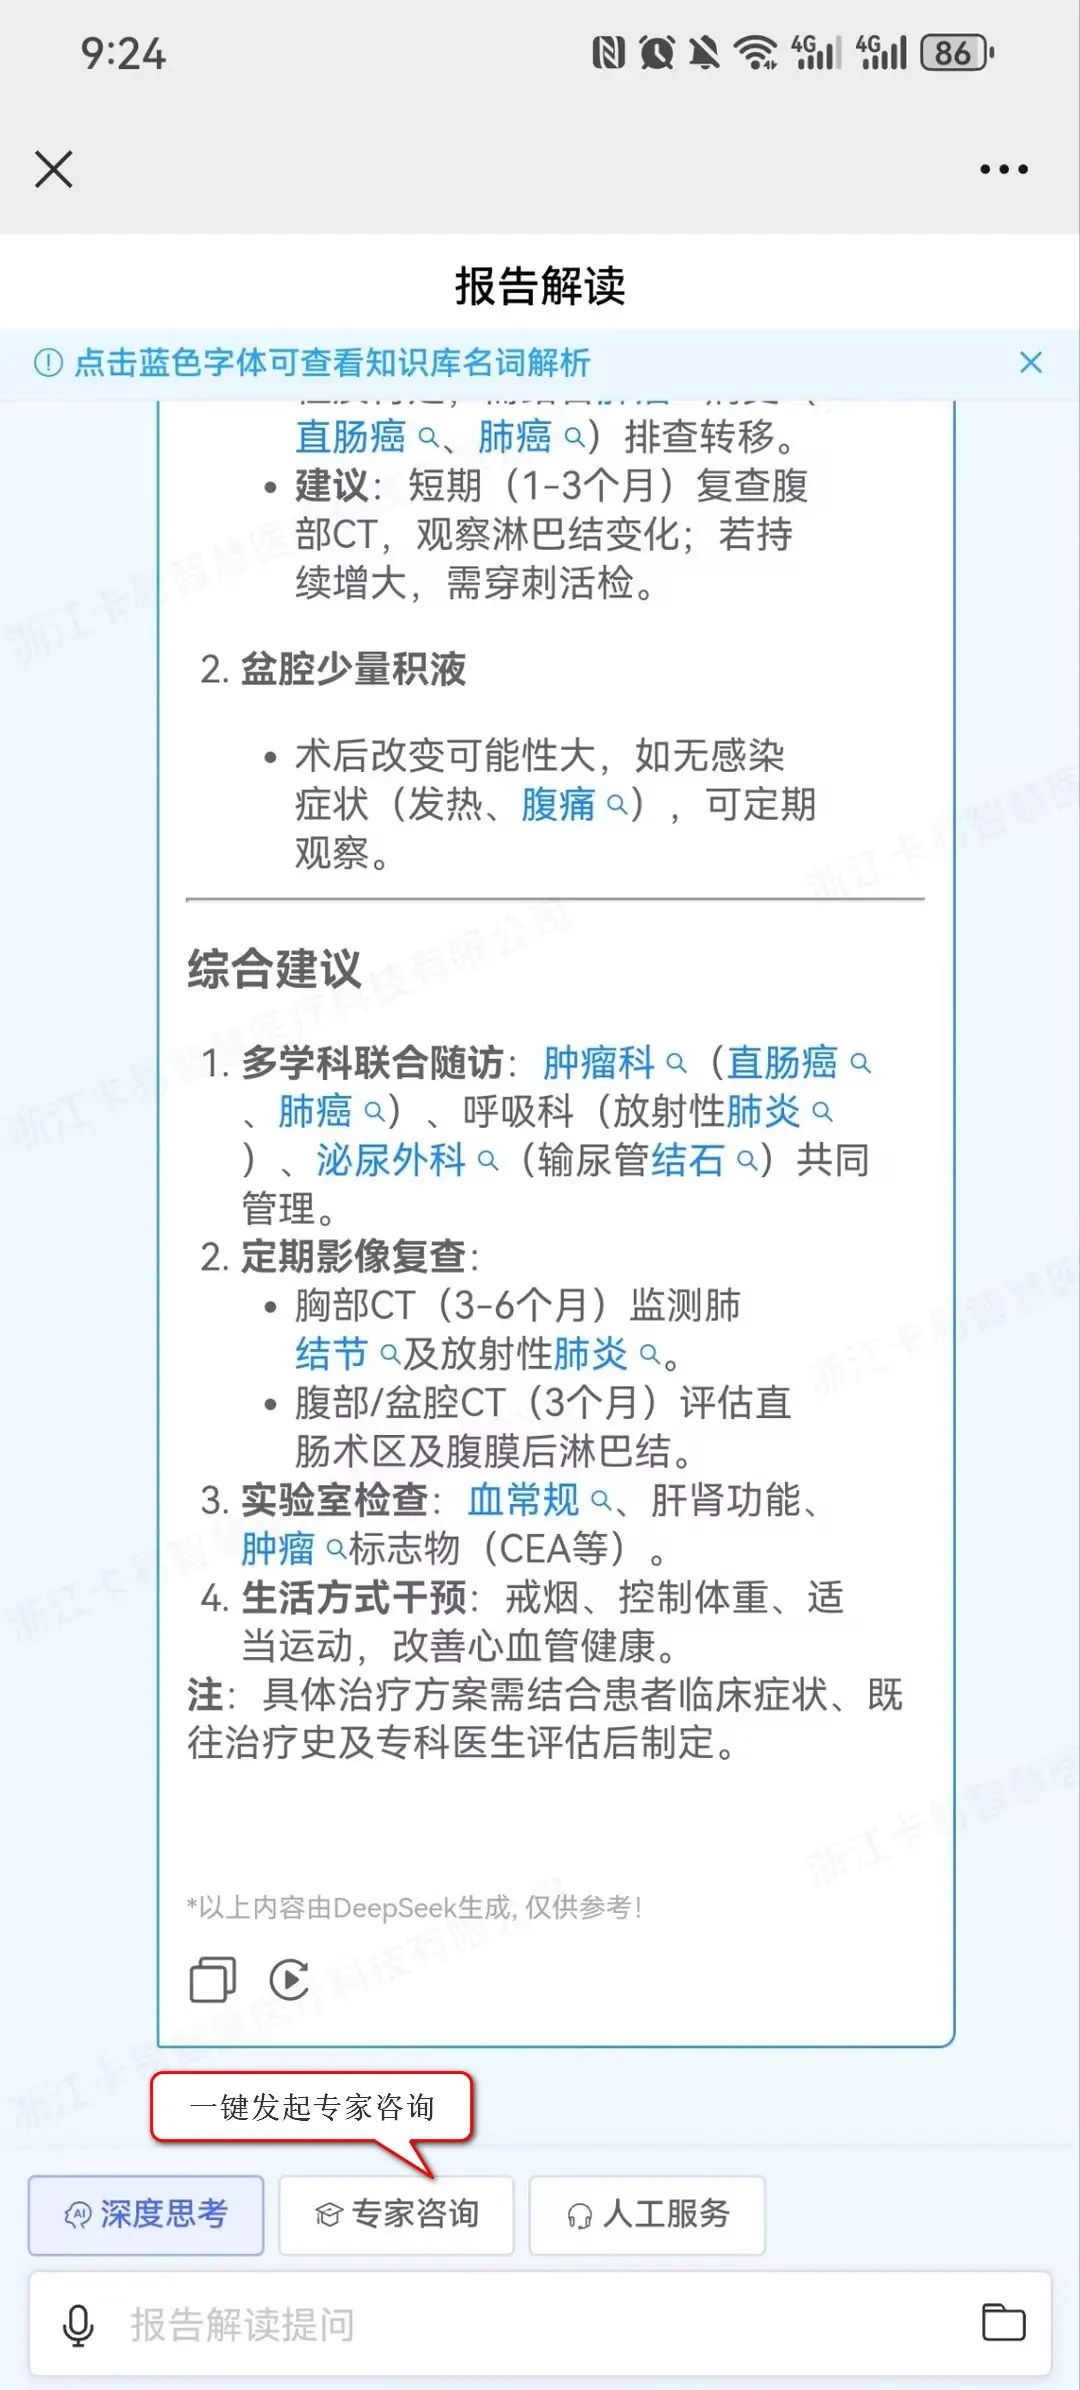

名词解析:点击蓝色字体可查看知识库名词解析,有助于患者更好地理解自己的病情、治疗方案以及预防措施,从而做出明智的健康决策。根据患者的病情和检查结果,推送相关的健康教育内容,例如疾病知识、预防措施、治疗方案等。

影像咨询:当患者对查看的影像或报告内容存在疑问时,可在报告界面直接发起影像咨询,借助DeepSeek获取关于检查流程、报告解读、病情咨询等方面的便捷、专业、优质且经济的建议与服务。若仍有不解,患者还可一键点击专家咨询,迅速发起线上问诊,由平台专家提供权威解答,这一流程不仅极大地优化了患者的就医体验,也显著提升了医疗服务的效率与质量。